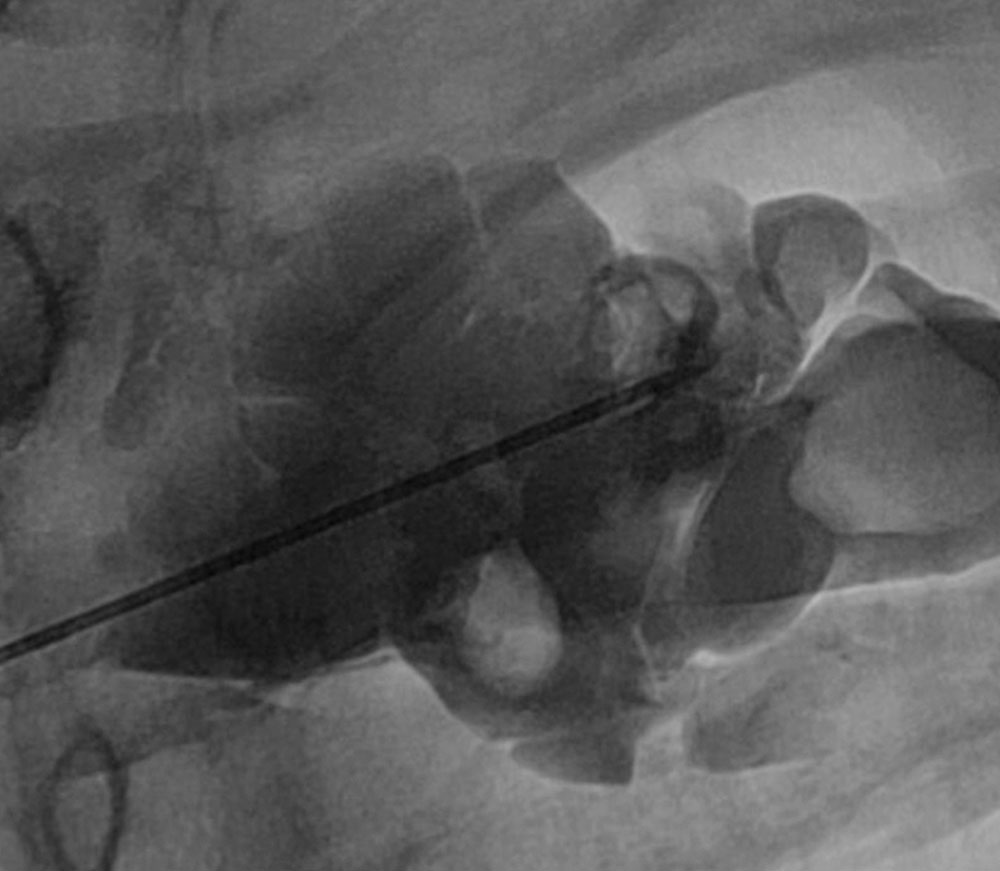

• Local sclerotherapy of the venous malformation by direct puncture under laryngoscopic control.

• Conventional induction of anesthesia with mask ventilation without problems.

• Direct laryngoscopy or intubation by an experienced senior anesthesiology physician was not possible.

• This was followed by microlaryngoscopy by a senior ENT physician.

• After several careful attempts, a 5.0 tube was successfully placed without manifest bleeding.

• After successful intervention, a repeat microlaryngoscopy was performed and the decision was made to proceed with primary extubation.